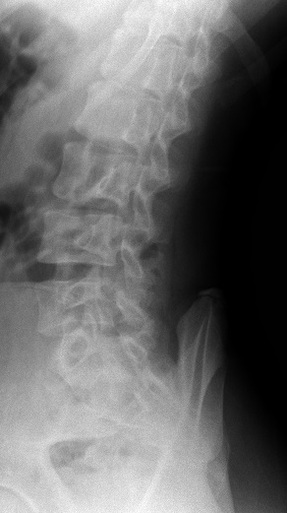

坂戸市若葉 中学生 腰が痛い 腰痛

レントゲン 正面像 レントゲン 斜位像

坂戸市若葉 中学2年生男子。 腰の痛み、腰痛。

小学生からサッカーのクラブチームに所属しています。半年前から腰が痛くて練習が思い切って

整骨院や整形外科で治療を受けてきましたが、腰の痛みは無くなりませんでした。当接骨院で

腰の痛みが半年と長かったのでいつも精査を依頼しているクリニックでレントゲン検査を実施

いたしました。腰椎の分離症やすべり症が心配でしたが、特に骨格にはに問題はありませんでした。

【治療】

やはり腰や股関節周囲の筋肉の緊張が非常に高まっていました。それらの筋肉を徹底的に柔軟に

していきます。当院独自の特殊仕様の治療機器を使用していきます。

男子はこれまでも日常的な腰痛とギックリ腰に悩まされてきましたが、腰部や股関節回りの

筋緊張を緩和することによって体感のバランスも調整され、将来の腰の痛みで椎間板ヘルニア

などの症状も予防できます。

半年間の痛みが数週間で消失しました。現在はクラブチームの練習を100%の力で行うことが

できています。男子のサッカーのパフォーマンスを最大限に引き上げるために、治療を継続中です。

当接骨院では場合によっては、整形外科や総合病院での検査を依頼することもあります。患者様には

なるべく負担の掛からない範囲で必要に応じて医療機関を紹介しております。